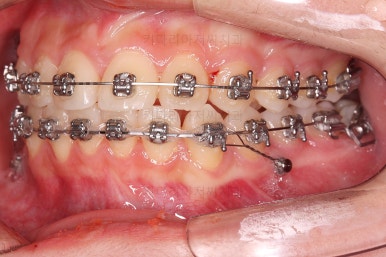

생각보다 많이 썩은 상태였어요.

앞쪽 치아 하방으로 갇혀 있으면서 훨씬 심각한 상태까지 충치가 진행되었던거죠.

우측 상단에 보이던 어금니도 바로 세운 뒤, 치료를 했습니다.(골드 인레이)

왼쪽 상단으로 보이던 치아도 치료를 했어요.

좌우의 치아가 재료가 차이가 나는데 한 쪽은 튼튼하고 오래 쓸 수 있고 광범위한 부위에 맞는 인레이라는 치료방법 입니다.

왼쪽 치아도 인레이가 추천되는 상황이었지만 경제적인 사정을 고려해서 일단은 건강보험이 적용되는 재료인 GI(지아이)라는 재료로 치료를 했슨비다. 성질이 약한 단점이 있어서 주기적인 체크가 굉장히 중요합니다.